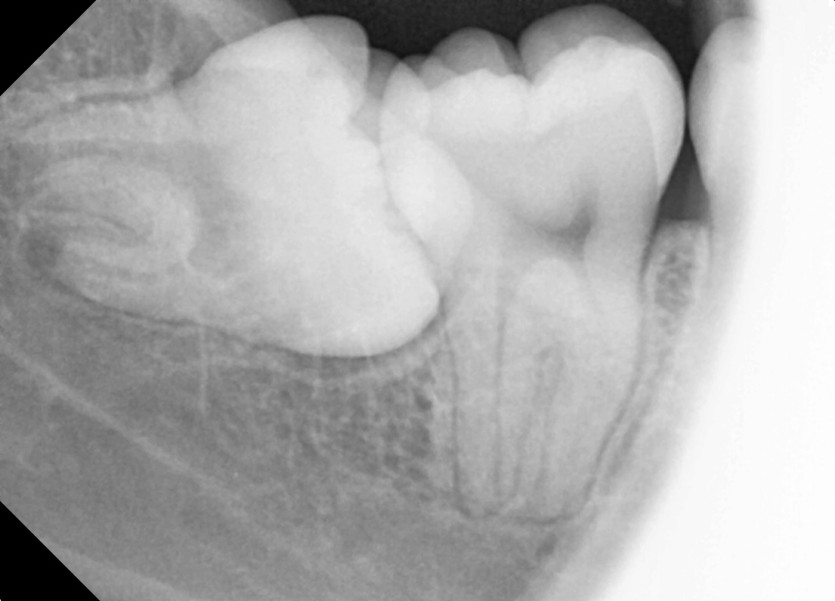

#38,48 사랑니 발치

구강 외과 전문의가 당일 발치했습니다.